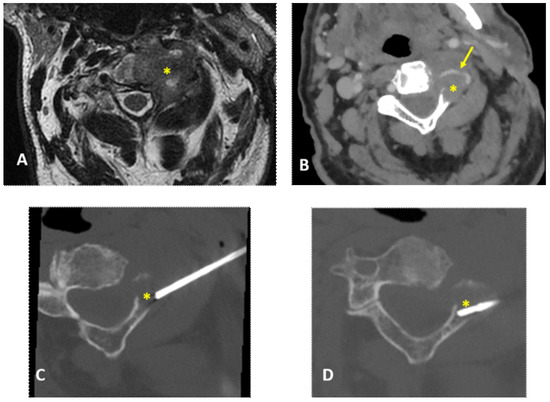

| 1 | 18, M | C2 | Osteolytic | 14 | No | Posterior | Aneurismal bone cyst |

| 2 | 71, M | C2 | Osteolytic | 14 | No | Posterior | Multiple myeloma |

| 3 | 49, M | C1 | Osteolytic | 14 | No | Posterior | Aggressive hemangioma |

| 4 | 64, F | C2 | Osteolytic | 14 | Yes | Lateral | Multiple myeloma |

| 5 | 64, F | C1 | Osteolytic | 14 | No | Posterior | Metastasis (breast cancer) |

| 6 | 40, F | C2 | Osteolytic | 14 | No | Posterior | Metastasis (breast cancer) |

| 7 | 39, M | C1 | Osteolytic | 14 | No | Posterior | Multiple myeloma |

| 8 | 16, M | C2 | Osteolytic | 14 | No | Posterior | Aneurismal bone cyst |

| 9 | 79, M | C2 | Osteolytic | 14 | Yes | Lateral | Non-diagnostic |

| 10 | 23, M | C1 | Osteolytic | 14 | No | Posterior | Blood and fibrin (non-diagnostic) |

| 11 | 73, M | C1 | Mixed | 14 | No | Posterior | Metastasis (prostate cancer) |

| 12 | 52, F | C0 and C1 | Osteolytic | 14 | Yes | Posterior | Multiple myeloma |

| 13 | 28, F | C1 | Osteolytic | 14 | No | Posterior | Aneurismal bone cyst |

| 14 | 72, F | C1 and C2 | Sclerotic | 12 | No | Posterior | Pseudogout |

| 15 | 51, F | C1 and C2 | Osteolytic | 14 | Yes | Posterior | Rare giant cells (non-diagnostic) |

| 16 | 86, F | C0 | Osteolytic | 12 | No | Posterior | Metastasis (breast cancer) |